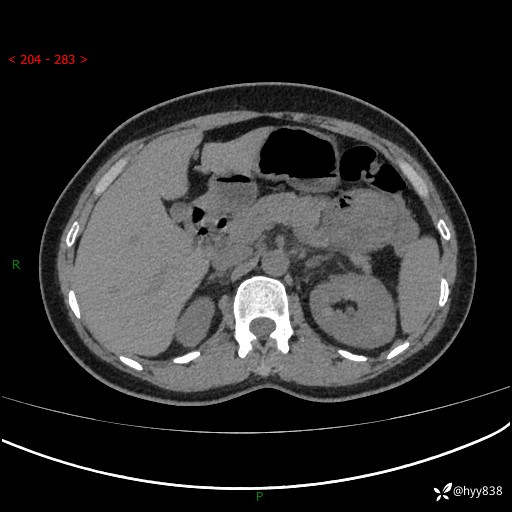

现病史:患者1天前无明显诱因下出现左上腹部及腰背部胀痛不适,阵发性加剧,伴肛门停止排气;无发热,无恶心呕吐,无畏寒发热,无心慌气短等不适,于当地市第二人民医院就诊,行腹部ct检查提示左上腹区肠系膜血管从剧聚集,分布紊乱伴肠管局限性稍扩张积液,不完全性肠梗阻;考虑子宫颈纳氏囊肿,双侧附件区囊状灶;予以抗炎及对症支持等治疗后未见明显缓解,现患者为求进一步治疗来我院急诊就诊,遂以“肠梗阻”收住入院。 病来,神志清,精神可,饮食睡眠不佳,经灌肠后排便2次,小便正常,体力体重无明显变化。

上腹部CT平扫